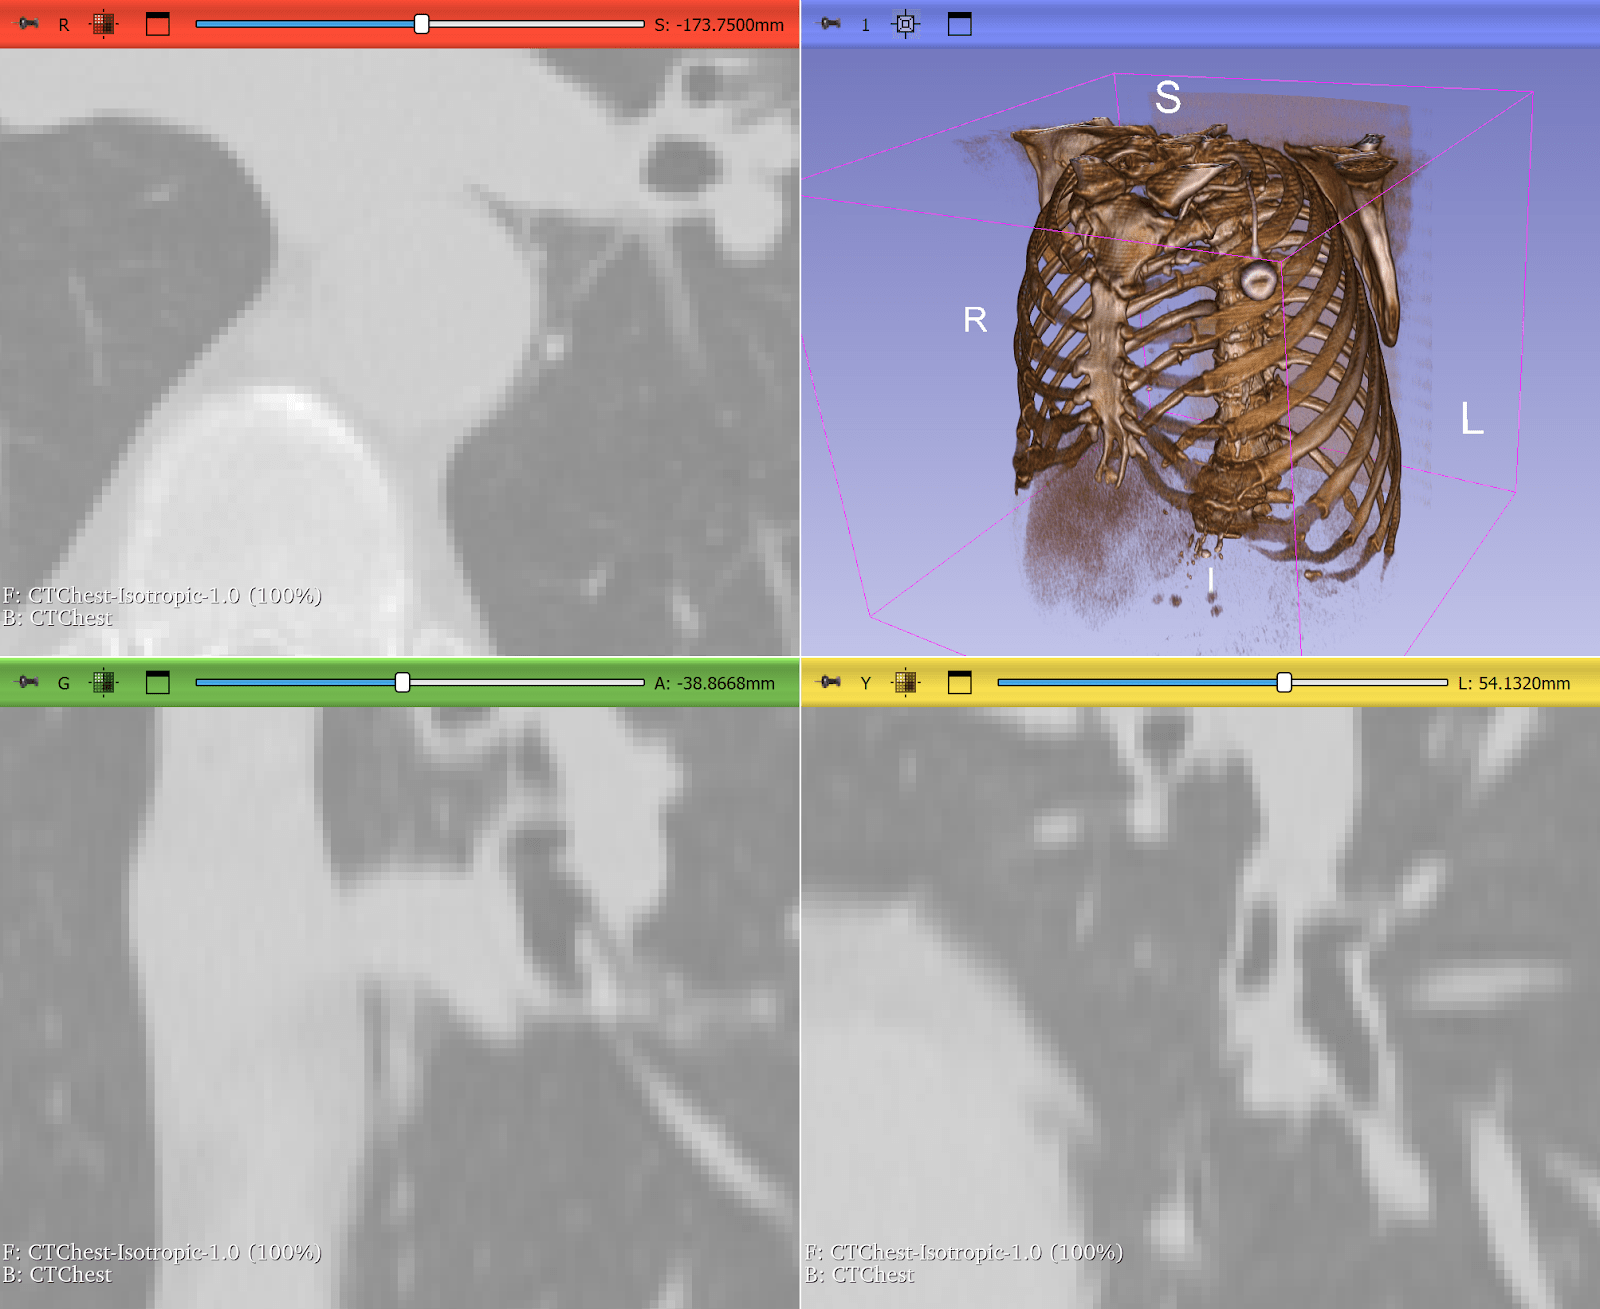

Resampling Lung CT Scans to Isotropic Voxels

Computed tomography (CT) scans often have anisotropic voxel spacing where the resolution along the axial slice direction is coarser than in-plane resolution. Deep learning models, especially 3D CNNs, perform poorly on such inconsistent geometry.

ITK provides robust resampling via the ResampleImageFilter, allowing researchers to convert CTs into isotropic voxel spacing (e.g., 1×1×1 mm³). This makes it quicker and easier to train deep learning models across heterogeneous datasets. In some cases, it can be as simple as:

This step is widely used in lung segmentation and COVID-19 CT analysis pipelines, where consistency in voxel geometry is critical for accurate volumetric measurements and model performance.

Figure 3: Lung CT before and after resampling, zoomed in with nearest neighbor resampling to show voxel sizes. Before: voxel size 0.76 x 0.76 x 2.5 mm. After: 1x1x1 mm. Use left-right slider to compare before vs. after.